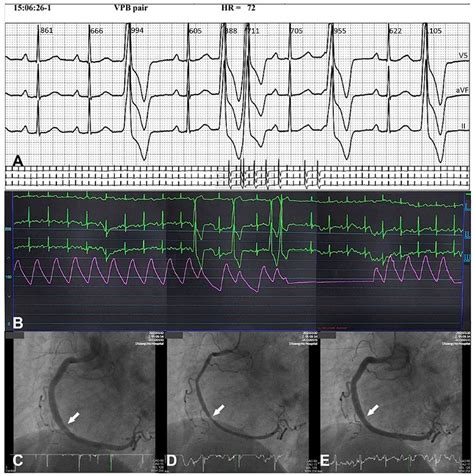

• Electrocardiogram (ECG): This test records the electrical activity of the heart and can detect abnormalities that may indicate arterial spasm.

• Coronary angiography: This invasive procedure involves inserting a catheter into the arteries to visualize blood flow and identify any blockages or spasms.